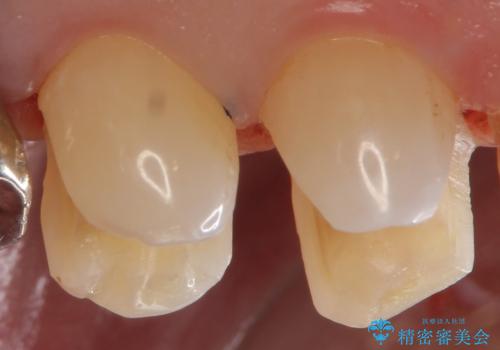

外から見える銀歯 セラミックでのやり替え

適合の良いセラミックインレーにやり替えることで外から見た時の違和感がなくなります。

また今回は治療前の写真で食べ物が詰まっている様子が伺えますが、適合がよく段差のない修復をすることで食べ物が詰まることを減らし、結果的に虫歯のリスクを下げることも期待できます。